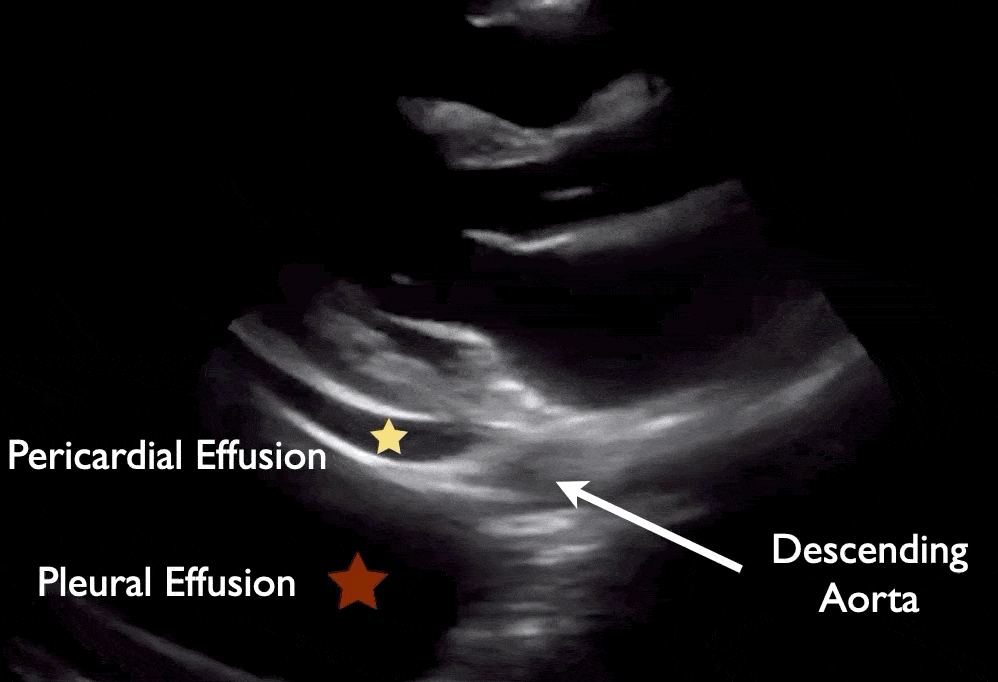

Large pericardial effusion in PLAX view.

Pericardial effusion is seen anterior to the descending aorta as portrayed in image. Pleural effusion is posterior to the descending aorta.